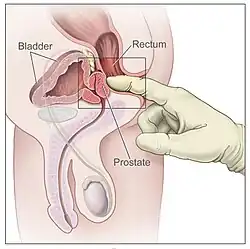

Prostatite é a inflamação da próstata. Pode ser causada por infecção por bactérias ou outras causas não infecciosas. A inflamação da próstata pode causar dor ao urinar ou ao ejacular, dor na virilha, dificuldade em urinar ou sintomas constitucionais, como febre ou canseira. Quando inflamada, a próstata aumenta de tamanho e fica sensível ao toque durante o exame retal. Uma bactéria culpada pode crescer em uma cultura de urina.[21]

Aumento da próstata

Uma próstata aumentada é chamada de prostatomegalia, com a hiperplasia prostática benigna (HPB) sendo a causa mais comum. HPB refere-se a um aumento da próstata devido a um aumento no número de células que constituem a próstata (hiperplasia) de uma causa que não é uma doença maligna. É muito comum em homens mais velhos. Frequentemente é diagnosticada quando a próstata aumenta a ponto de tornar a urinação difícil. Os sintomas incluem necessidade de urinar com frequência (polaquiúria) ou demorar um pouco para começar (hesitação urinária). Se a próstata ficar muito grande, ela pode contrair a uretra e impedir o fluxo de urina, tornando a urinação dolorosa e difícil ou, em casos extremos, completamente impossível, causando retenção urinária. Com o tempo, a retenção crônica pode fazer com que a bexiga cresça e cause um refluxo da urina para os rins (hidronefrose).[21]

- Muitas pessoas que possuem próstata, principalmente homens cis, negligenciam os cuidados com o órgão por acharem o exame vexatório. Entretanto, o exame de próstata é essencial para a manutenção da saúde, podendo detectar doenças em estágio inicial e tratável.